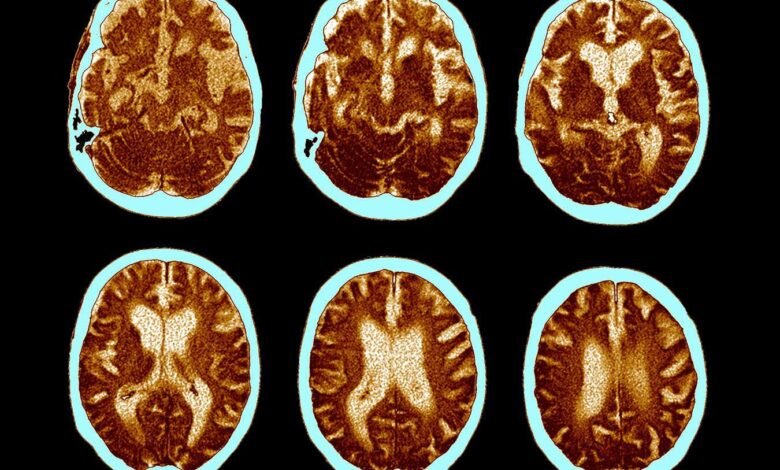

The brain shrinkage observed in Alzheimer’s may be prevented by semaglutide, the drug in Ozempic

ZEPHYR/Science Photo Library/Alamy